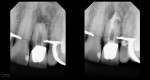

This was interesting because a root frac ture was seen where the prior apico was done. The MTAS was removed and Brassler putty used in this case. Will take a 1 yr CBCT and we will know more. Don’t usually get so much scar formation–so this was surprising…..